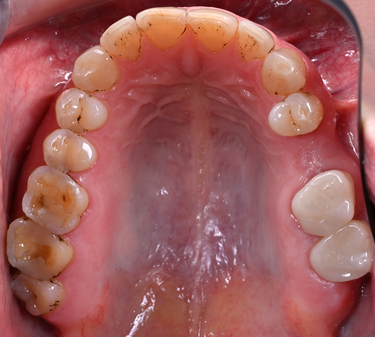

Figure 12: Upper jaw - before

Figure 14: Lower jaw - before